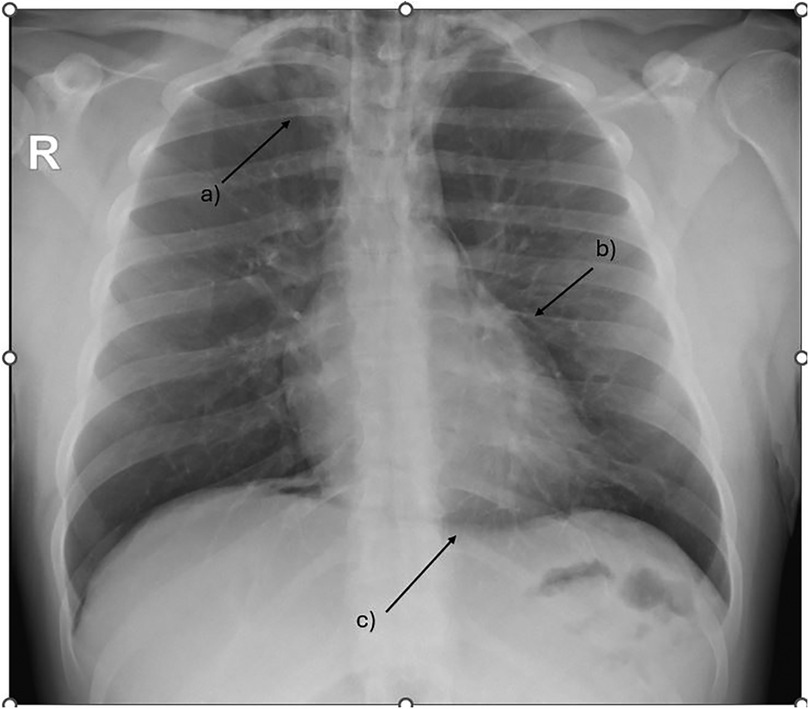

During acute coronary syndrome (ACS) exclusion workouts, transthoracic echocardiography images were very difficult to obtain, as hyperechoic moving artifacts were interfering with the ultrasound probe. Immediate chest x-ray showed massive pneumomediastinum (Figure 1). A subsequent CT scan confirmed the massive pneumomediastinum (Figure 2) and revealed the presence of an acute bilateral pulmonary embolism (Figure 3). Laboratory tests showed elevated D-Dimer levels (2,515 ng/mL), polycythaemia (hemoglobin 18.9 g/dL, haematocrit 55.5%), and slightly elevated creatinine (1.48 mg/dL, creatinine clearance 49 mL/min) with mild hypoalbuminemia (3.2 g/dL).

Figure 3

CT scan—CTPA demonstrates saddle pulmonary embolism extending to subsegmental branches bilateral (arrow demonstrates a large thrombus extending across the pulmonary artery bifurcation).